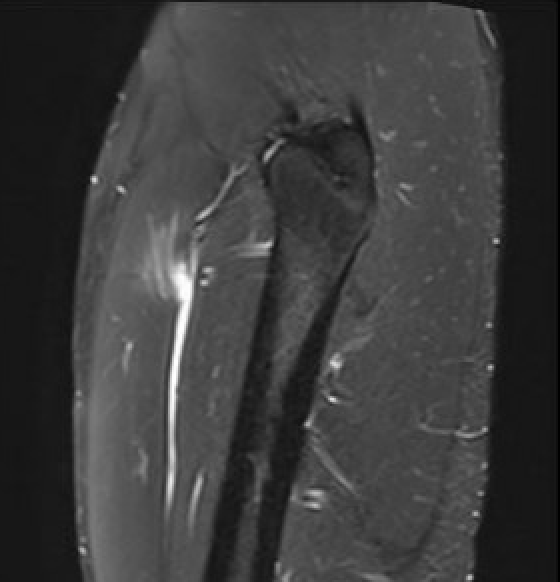

Grade 3B proximal rectus femoris muscle